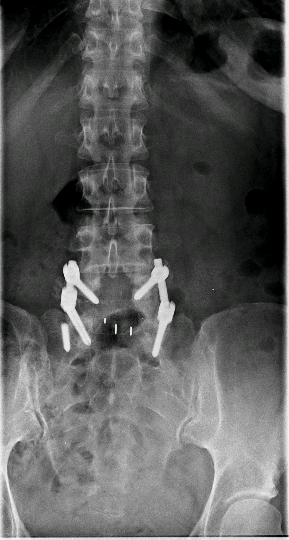

Paciente intervenido hace más de 3 años L5-S1 en otro centro que presenta recidiva de la clínica por la que se operó. En RX se evidencia ausencia de fusión.

Obsérvese la fractura del tornillo caudal como signo de ausencia de fusión.

Se realiza TLIF L5-S1 recolocando el tornillo de S1 en un trayecto más craneal.